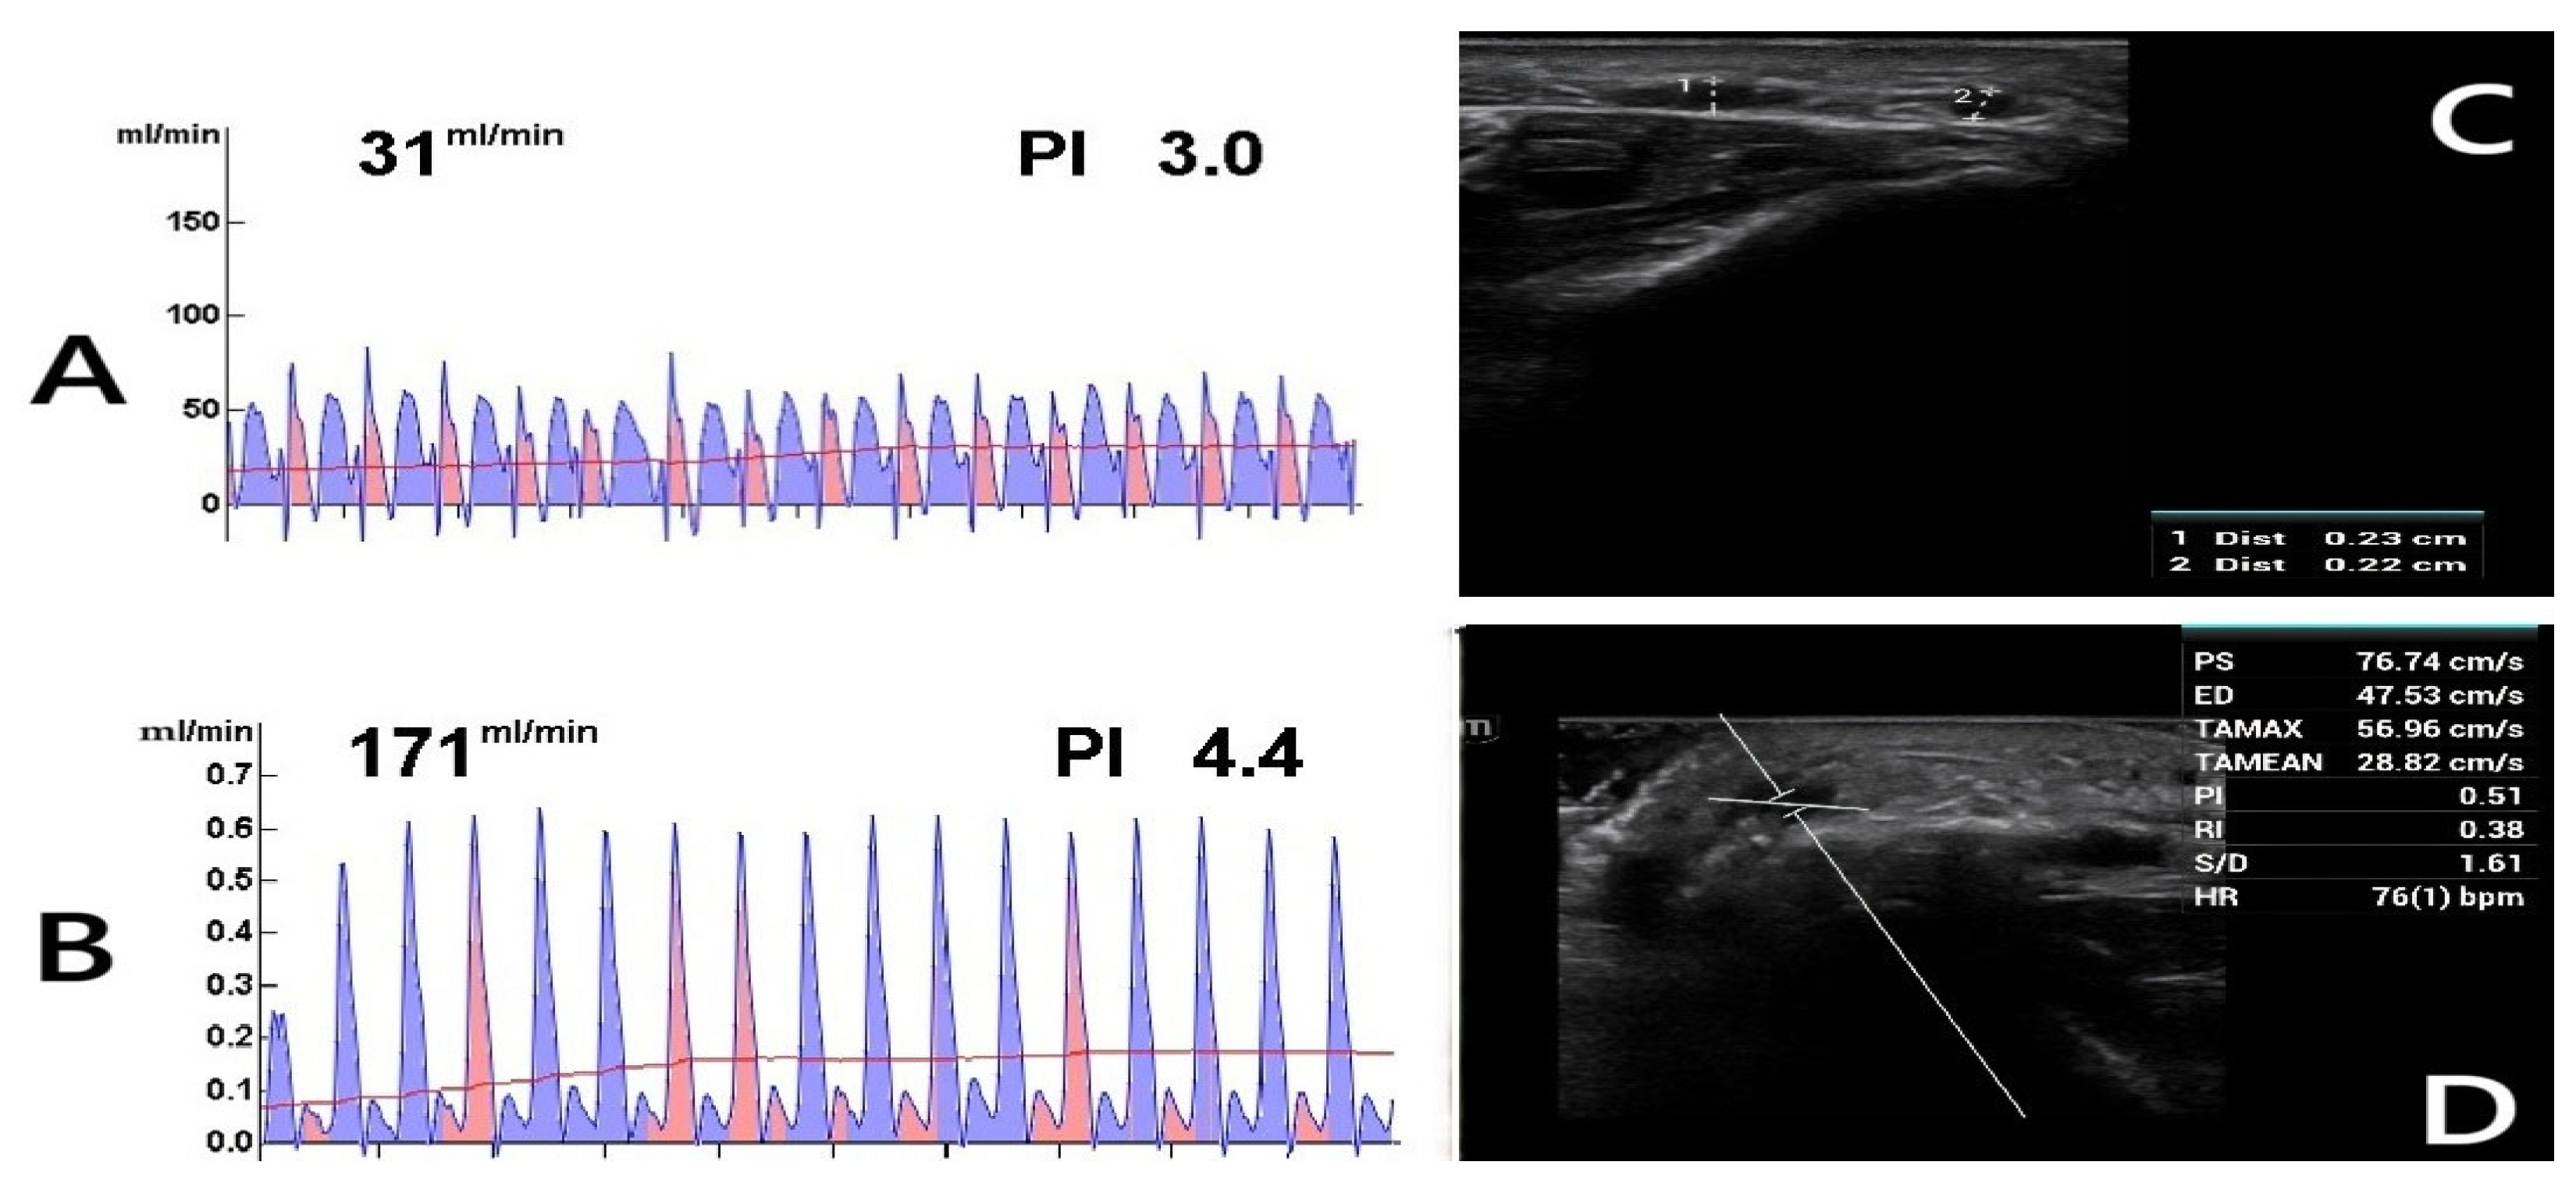

For radiocephalic fistulas, the mean arterial and venous diameters were 2.9 ± 0.6 mm and 3.1 ± 0.5 mm, respectively, in females, and 3.1 ± 0.4 mm and 3.2 ± 0.8 mm, respectively, in males. In brachiocephalic fistulas, females exhibited mean arterial and venous diameters of 3.9 ± 1.1 mm and 3.5 ± 0.8 mm, respectively, whereas males had corresponding measurements of 4.8 ± 0.5 mm for the artery and 4.0 ± 0.5 mm for the vein. The mean vascular diameters, calculated as the combined averages of both arterial and venous structures in the brachial and radial regions, were assessed. This approach was necessary because, among females, AVFs were predominantly created using the brachial artery (40 patients), with only 10 cases utilizing the radial artery. In contrast, the brachial artery was selected in 18 male patients due to inadequate radial circulation or small vein diameters (<2 mm). The arterial diameter was significantly greater in females than in males (3.8 ± 0.4 mm vs. 3.61 ± 0.9 mm; p = 0.013), whereas venous diameters were similar between sexes (3.3 ± 0.5 mm in females vs. 3.2 ± 0.4 mm in males; p = 0.118). Despite having larger arterial diameters, females exhibited significantly lower intraoperative blood flow rates compared to males based on TTFM measurements (median: 200 mL/min vs. 289 mL/min; p < 0.001). Additionally, females displayed higher vascular resistance, indicated by a greater PI (2.6 vs. 1.6; p < 0.001). These results highlight that AVF performance relies not only on vessel size but also heavily depends on individual vascular quality and blood flow dynamics (Figure 1A–C).

Figure 1.

Transit-Time Flow Measurement (TTFM) and probe application. The images demonstrate TTFM use during brachiocephalic AVF creation in a 45-year-old male patient. (A) Measurement of the brachial artery before AVF creation shows adequate arterial flow. (B) After AVF creation, the probe placed on the vein (C) shows good flow measurements. The Pulsatility Index (PI) of 0.7 and Diastolic Filling (DF) of 60% indicate low resistance and effective blood flow continuity, essential for proper AVF maturation (brakiosefalik fistül; brachiocephalic fistula in English).